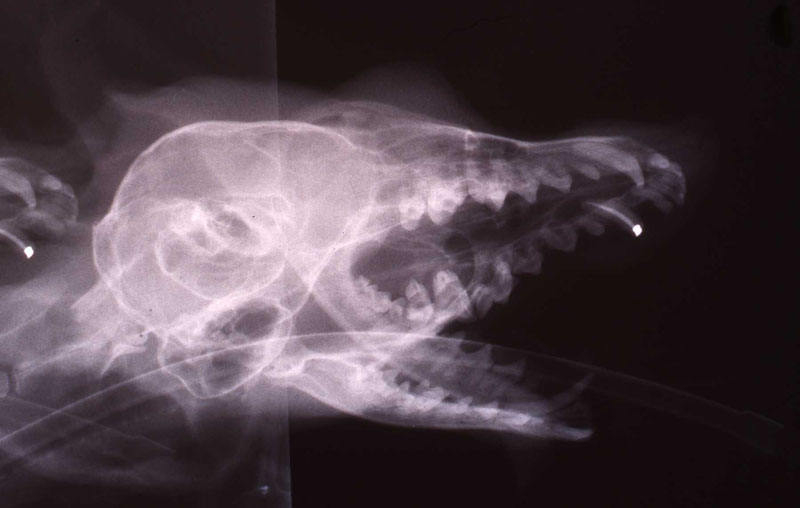

Knowledge of the particular tooth anatomy and dimensions is critical. In particular, understanding of the delta foramen in all carnivore teeth is essential to treatment considerations. The delta foramen presents a microscoptic anatomy that is impossible to instrument. If the pulp has become necrotic in the delta area it is very questionable whether instrumentation and irrigation disinfects the delta region. If the conventional, coronal or oblique approach fails, or the apex is open from being immature or destroyed by lysis, a surgical approach is appropriate. That would involve an apisectomy, retrograde approach and fill. I will describe that later. See Reference section Topic: The Delta foramina. Studying skull and teeth specimens is the best manner of such preparation.We have developed a collection of skulls and teeth from animals that have died at MCZ. We have also cultivated relationships with the Milwaukee Public Museum and University of Wisconsin Zoology Museum for access to their collection. See pix of hyena canine and cutaway of its pulp chamber and the delta foramen anatomy.

1. Fennec Fox, maxillary canine endodontic therapy